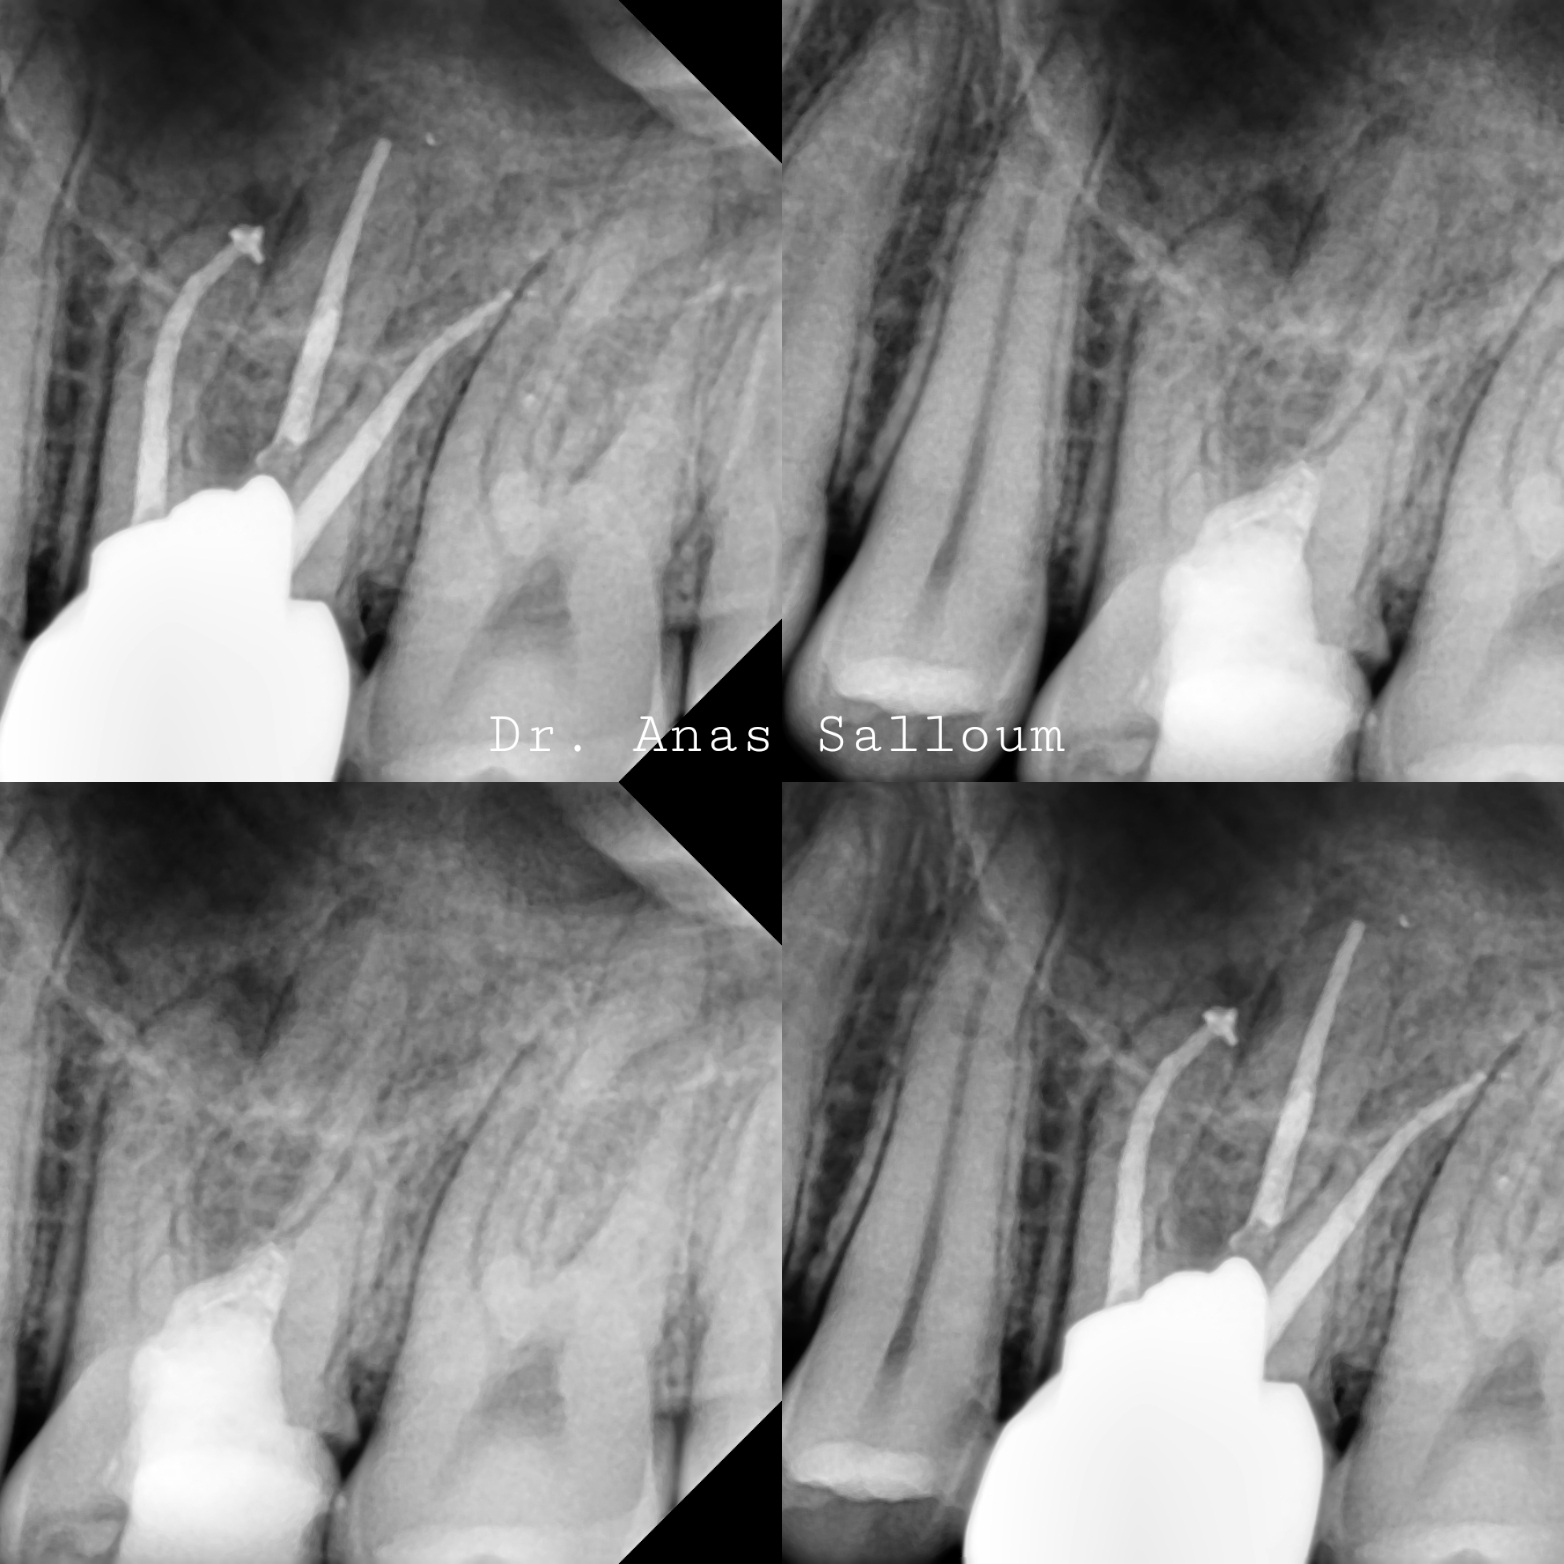

• Clinical examination & digital X-rays

Root canal therapy is a dental procedure that removes infected pulp from inside the tooth, disinfects the root canal, and seals it to prevent future infections.